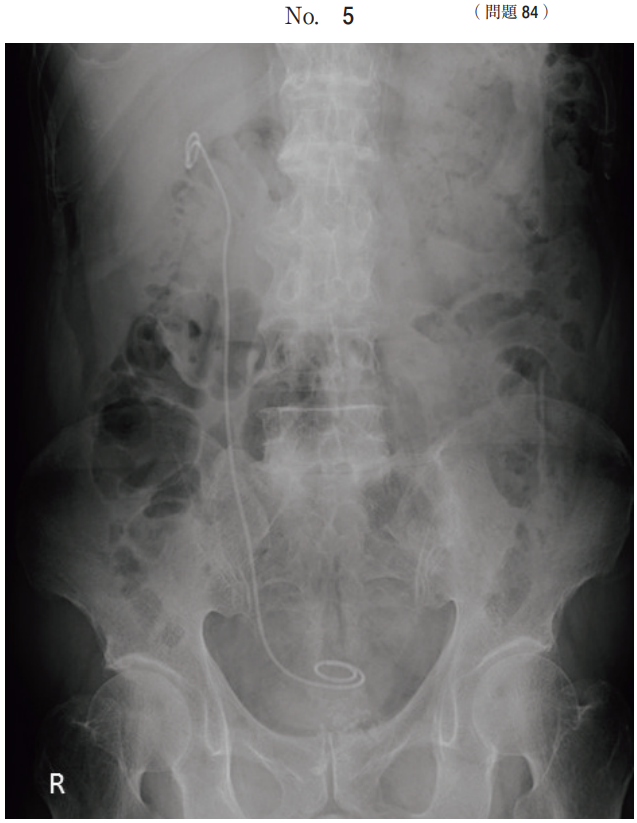

午前/問題84

KUB の画像(別冊No. 5)を別に示す。

行われた処置はどれか。

1.人工血管置換術

2.尿管ステント留置術

3.消化管ステント留置術

4.イレウスチューブ挿入術

5.腹部大動脈ステントグラフト留置術

答え

2